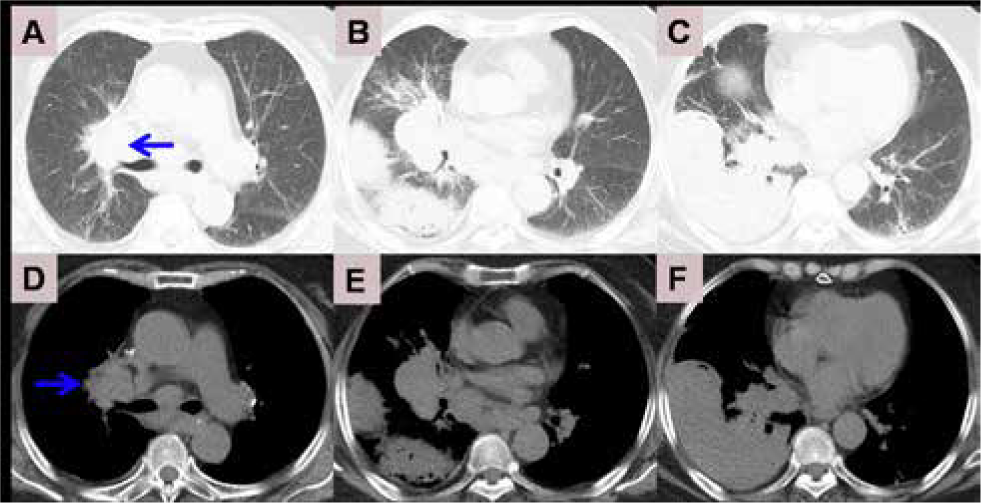

A 71-year-old female was taken to our hospital after experiencing bilateral chest pain and dyspnea for 20 days. She had no other complaints, such as fever, cough and bloody sputum. The patient had a history of arthritis pauperum for 20 years, and denied traditional Chinese medicines for treatment. She had no personal history of smoking and family history of cancer. On clinical examination, no palpable lymph nodes and hepatosplenomegaly were found. There was no obvious rale in bilateral lungs. Computed tomography (CT) of the chest demonstrated a high density shadow in the right middle lower lobe and left lower lobe, and air bronchogram was obvious (Figure 1 C). Bilateral hilar masses exits (Figure 1 E) and low density area was visible (green arrow). Mediastinal lymph nodes enlarged. The crescent shaped liquid density was in right pleura (Figure 1 D). CT of abdomen showed no abnormalities. Bone marrow biopsy showed no infiltration. CT-guided transthoracic core needle biopsy was performed (Figure 2). Pathological section demonstrated diffuse large B cell infiltration in small fibrous tissue. Immunohistochemical staining showed Mum-1(-), Ki-67 index 70%, Cyclin D1(-), CD43(+), CD5(+), Bcl-2(-), CD3(-), CD79a(+), CD23(-), CD10(-), Bcl-6(-), Syn(-), CD20(++), CD56(-) (Figure 3). Based on these findings, PPDLBCL was diagnosed. Due to personal reasons, the patient underwent cyclophosphamide pirarubicin vindesine dexamethasone (CHOP) chemotherapy without rituximab, which was planned to be repeated every 21 days for 6 cycles. Following the administration of 6 cycles of CHOP chemotherapy, chest pain and dyspnea were alleviated. Nevertheless, CT demonstrated bilateral masses and consolidation partially diminished (Figure 4 E F), while a new mass emerged in the right upper lobe (Figure 4 A D blue arrow). Unfortunately, at 9 months of follow-up, the patient died.

Chest computed tomography after 6 cycles of chemotherapy. A B C; mediastinal window: D E F. Blue arrow indicates newly emerging mass.